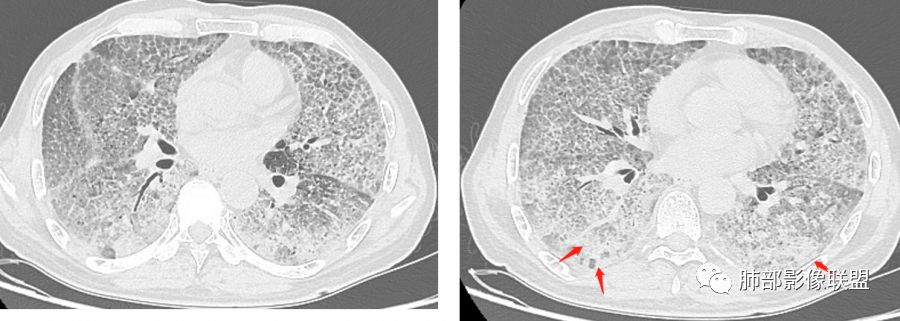

徐婕:双肺弥漫磨玻璃,铺路石,部分斑片实变。病程一年,血白细胞增高,考虑肺泡蛋白,合并双肺感染?鉴别腺癌

八爪:弥漫分布磨玻璃密度影,小叶间隔增厚,典型铺路石征,考虑PAP伴发感染性病变,鉴别特发性间质性肺炎,弥漫性腺癌,建议支气管灌洗;左肺上叶舌段不规则团片状阴影,显示不清,密切随访

小谢:慢性病程,无发热,双肺弥漫性病变,GGO,铺路石征,首先考虑PAP,鉴别肺腺癌

我心飞翔:中年男性,双肺弥漫磨玻璃影,铺路石征,病灶内可见扩张支气管,CEA高,血象高,黄痰,考虑PAP并感染,腺癌待排

郑氏刀刀:双肺弥漫性磨玻璃影,伴铺路石征,下叶为主,且见斑片实变影,白细胞高,结合执业史,尘肺,PAP伴感染,腺癌待排。

小赵:中老年男性患者。慢性病程,多次咳黄痰,治疗效果一般,反复发生。CT表现为双肺弥漫磨玻璃样改变,并呈细网格样铺路石状改变,上下肺无明显差异。双下肺为主多发渗出实变,边界不清,抗炎治疗后病变吸收不明显,局部似有进展。考虑肺泡蛋白沉积症基础上合并感染。肿瘤标志物高,中老年患者,肺炎型肺癌不除外。

1、GGO+网格——碎石路征

2、分布无特定位置,较随机

3、可有少许实变——部分与层厚有关

4、小叶间隔内静脉增粗

5、病灶较多时部分可见重力趋势

1.由于脂蛋白的沉积和占据,肺泡腔含气量减少,这是影像上较大范围“磨玻璃影”的基础。

2.由液体、细胞浸润和纤维组织造成的小叶间隔增厚是影像上多边形“铺路石征”的基础。

3.显眼的小叶间隔对病灶有阻挡作用是形成影像上“地图样改变”的基础。我们观察到的病灶与临近相对正常肺组织之间常常有比较清楚的分界。